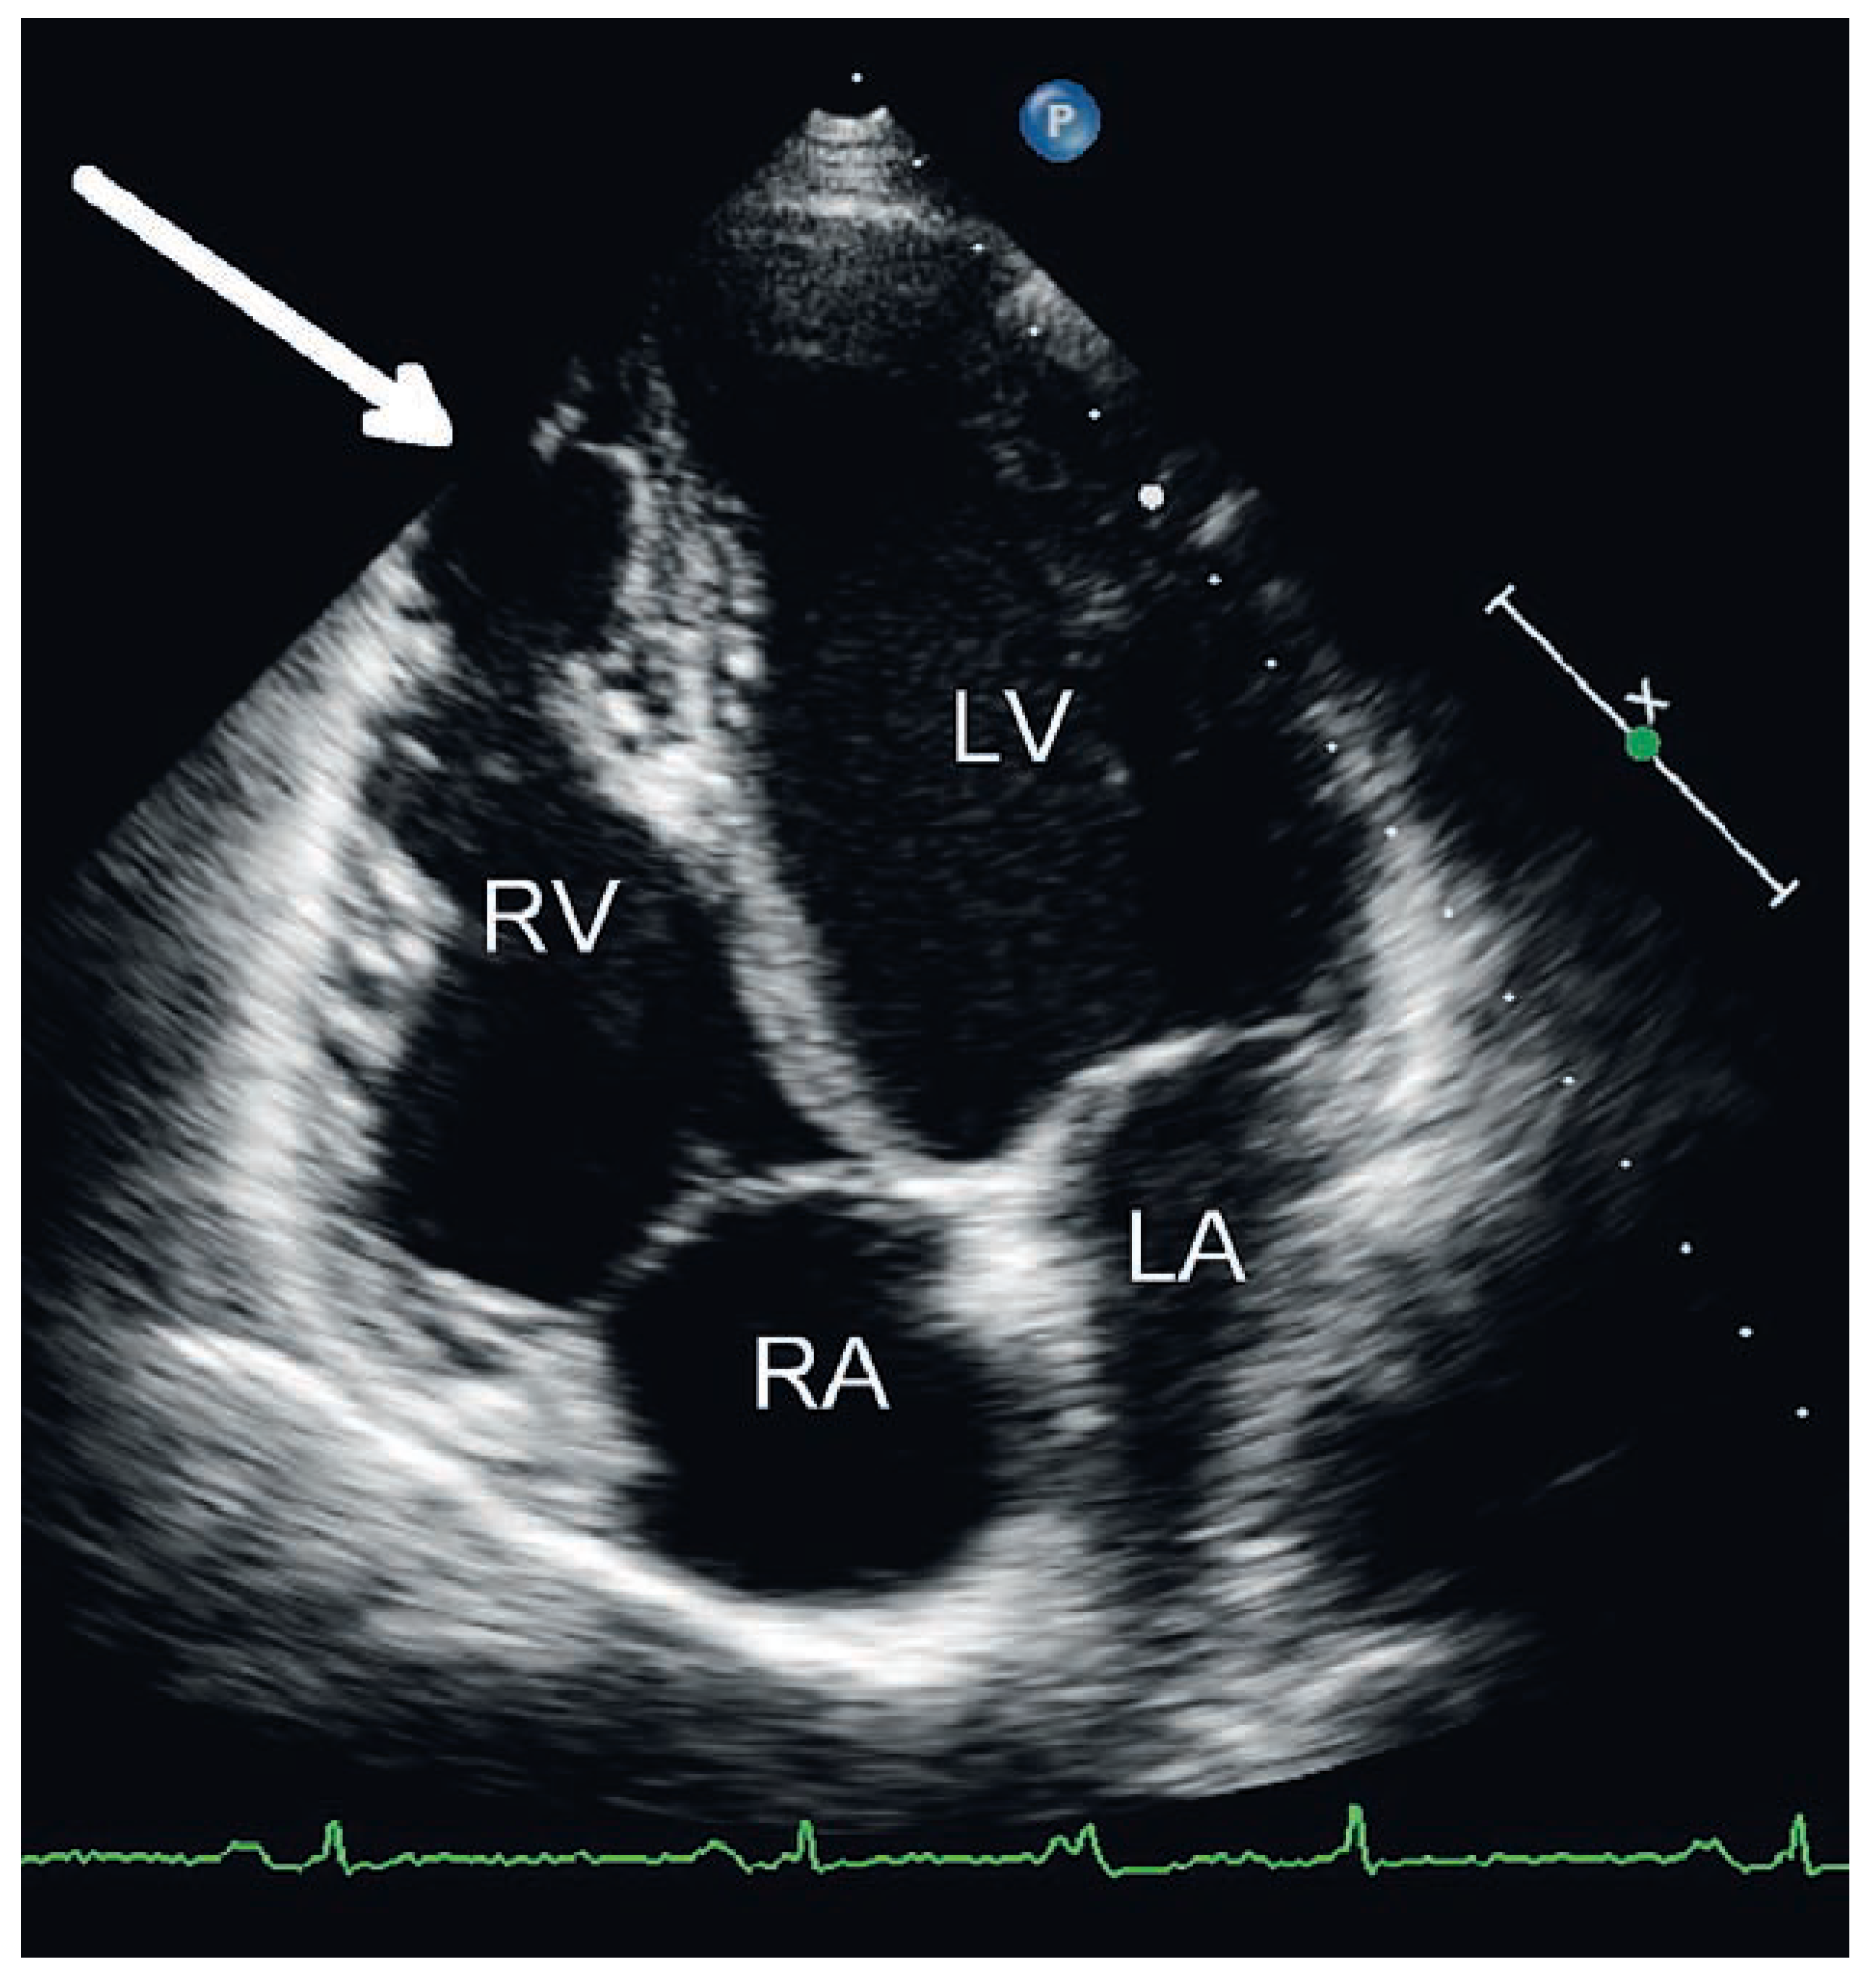

Ursprung der Extrasystolen

Fallbeschreibung